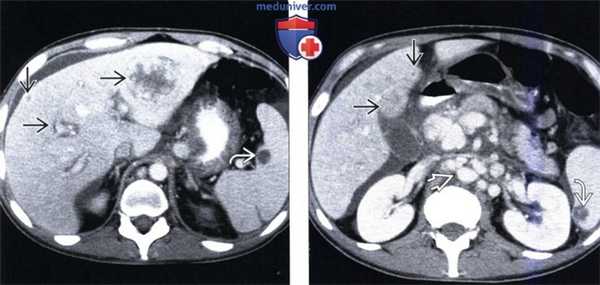

(Слева) На КТ в артериальной фазе контрастного усиления у женщины 32 лет, страдающей, как и ее родственники, носовыми кровотечениями, определяется неравномерное накопление контраста в паренхиме печени, а также раннее заполнение контрастом расширенных печеночных вен.

(Справа) На КТ в артериальной фазе контрастного усиления у этой же пациентки определяется неравномерное контрастирование паренхимы печени, раннее заполнение расширенных печеночных вен и нижней полой вены, а также расширение и извитой ход печеночной артерии (Слева) На аксиальной КТ в портально-венозной (печеночной паренхиматозной) фазе контрастного усиления у этой же пациентки печень в целом выглядит обычно, за исключением расширения печеночных вен и НПВ, что указывает на наличие интрапаренхиматозных шунтов, по которым происходит «сбрасывание» крови, из-за чего в артериальной фазе печень выглядела неоднородной.

(Справа) На КТ в венозной фазе контрастного усиления у этой же пациентки визуализируется одно из двух гиподенсных образований неизвестной природы, не меняющих размер в течение нескольких лет. (Слева) На рентгенограмме (катетерная ангиография) у этой же пациентки визуализируются расширенные артериальные сосуды, многочисленные участки повышенной плотности, неправильной формы, а также множественные ангиэктазии.

(Справа) На рентгенограмме (катетерная ангиография) у этой же пациентки определяется раннее заполнение контрастом расширенных вен. Катетерная ангиография редко используется для оценки выраженности изменений при НГТ, и большей частью заменяется КТ-либо МР-ангиографией.